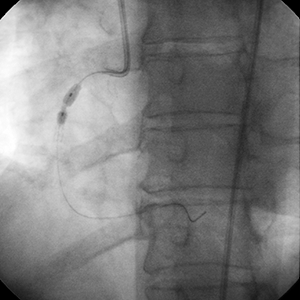

Posdilatación

• Se usaron balones de alta presión de 3,5 mm y 4 mm para postdilatar el stent.

• Los balones de alta presión no tuvieron éxito en la optimización de la expansión del stent.